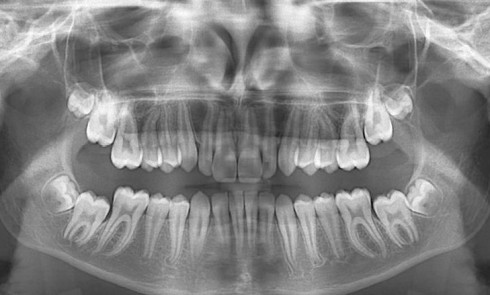

Article réservé à nos abonnés Amélogenèse imparfaite et maladie rare : réhabilitation par prothèses amovibles

L’amélogenèse imparfaite (AI) est un groupe de maladies héréditaires hétérogènes sur le plan génétique et phénotypique qui affecte la qualité...